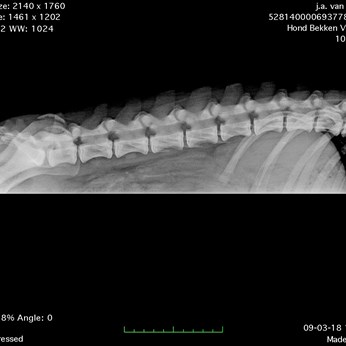

Name: Andrea von Haus Ka und Mi (Duuts)

Gender: Female

Date of birth: 28-06-2017